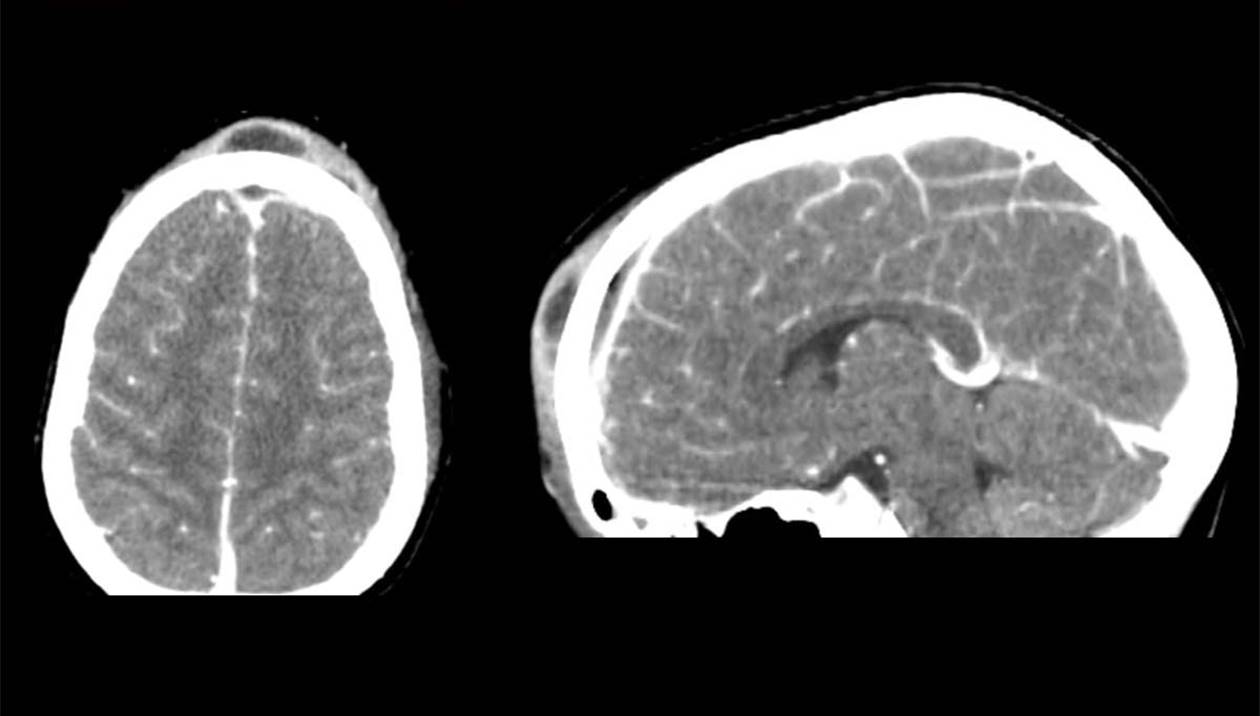

«Ένα πολύ σοβαρό περιστατικό αντιμετωπίζεται αυτές τις μέρες με επιτυχία στο νοσοκομείο μας. Παιδί 8 ετών, με βαριά επιπλεγμένη ρινοκολπίτιδα, μεταφέρθηκε εσπευσμένα στο Πανεπιστημιακό Νοσοκομείο Ηρακλείου. Ο κλινικός και απεικονιστικός έλεγχος ανέδειξαν βαριά μετωπιαία κολπίτιδα και οστεομυελίτιδα, ηθμοειδίτιδα, καθώς και συνοδό ενδοκρανιακό απόστημα. Η ζωή του παιδιού κινδύνευε σοβαρά και αποφασίστηκε χειρουργική αντιμετώπιση. Στο χειρουργείο, υπό γενική αναισθησία, παροχετεύσαμε επιτυχώς το πύο από το μετωπιαίο κόλπο και τις ηθμοειδείς, με ενδοσκοπική προσπέλαση. Ακολούθως, οι νευροχειρουργοί διενέργησαν ανοικτή κρανιοτομή και παροχέτευσαν το υποσκληρίδιο απόστημα του εγκεφάλου. Η ανταπόκριση του μικρού ασθενούς ήταν εντυπωσιακή. Μετά από σύντομη παραμονή στη ΜΕΘ Παίδων, βρίσκεται πλέον, σαφώς βελτιωμένος, στην παιδιατρική κλινική.  Η συνεργασία όλων των εμπλεκόμενων ειδικοτήτων, ΩΡΛ, νευροχειρουργών, αναισθησιολόγων, παιδιάτρων και εντατικολόγων, ήταν εξαιρετική. Και η συμβολή όλων καθοριστική ώστε να διαφύγει τον κίνδυνο ο μικρός ασθενής μας».